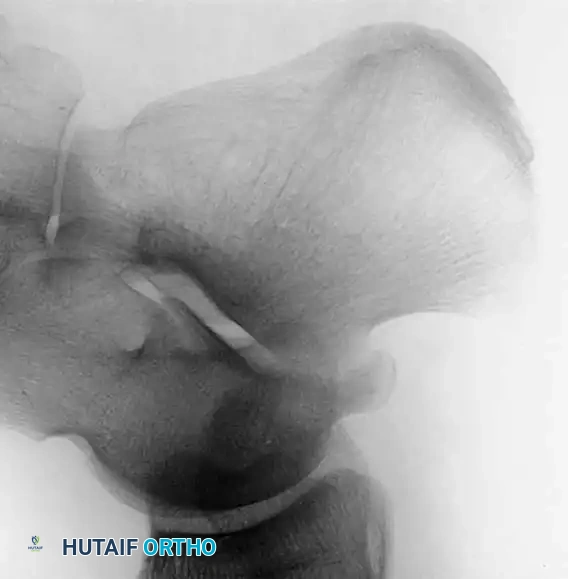

بناء الرباط الصليبي الأمامي

لا يمكن خياطة الرباط الصليبي الأمامي الممزق، بل يجب إعادة بنائه باستخدام رقعة نسيجية بديلة.

* اختيار الرقعة: يمكن أخذ الرقعة من جسم المريض نفسه مثل وتر الرضفة أو أوتار المأبض، أو استخدام رقعة من متبرع.

* التقنية الجراحية: يتم حفر أنفاق دقيقة في عظمة القصبة وعظمة الفخذ في المواقع التشريحية الدقيقة للرباط الأصلي، ثم يتم تمرير الرقعة وتثبيتها باستخدام مسامير تداخلية أو أزرار تعليق قشرية.